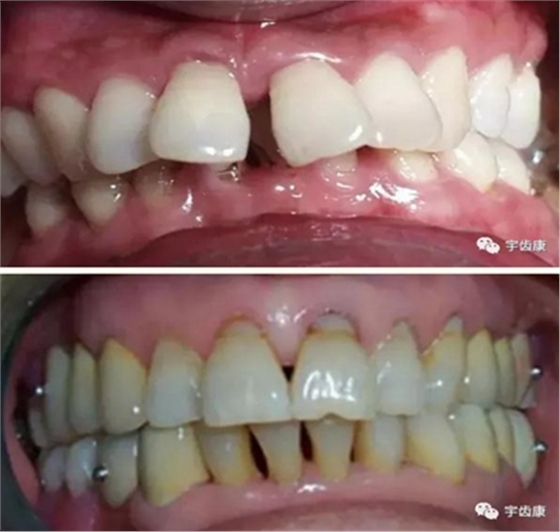

實際備牙產(chǎn)生的問題

8. 實際備牙產(chǎn)生的問題